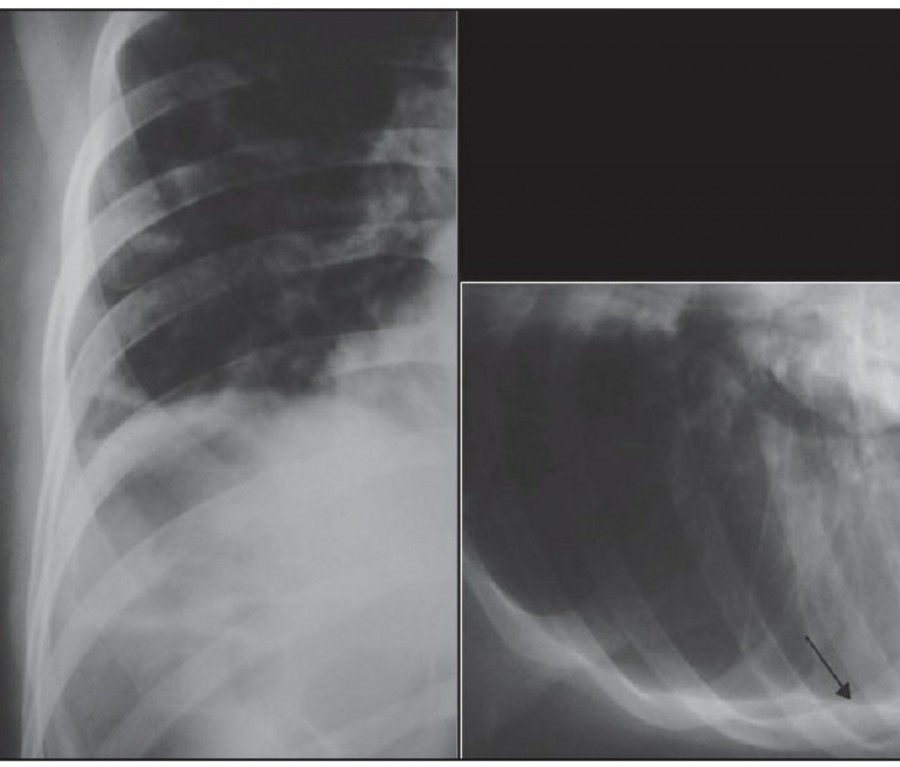

방사선 소견상 Pleural effusion은 환자 흉부의 dependent area에 고인다. Erect position에서 확인하기가 쉬운데, 폐의 base에 고임으로써 costophrenic angle blunting을 보이고 lower lobe vessel들의 흐리게 한다. Supine position에서는 확인이 더 어려운데, pleural fluid는 posterior basilar space에 고여서 폐 base 쪽으로 intensity가 증가하는 homogenous density를 보인다. 정상적인 bronchoalveolar marking은 이와 같은 veil-like density 안에서 확인 가능하다. Fluid 양이 늘어나면서 diaphragm의 윤곽이 흐릿해지고 costophrenic angle도 없어지는데, 이 costophrenic angle blunting이 없더라도 pleural space에 1L 정도의 pleural fluid가 있을 수 있다는 것을 기억해야 한다. 그 양이 더욱 늘어날 수록 fluid는 lung의 apex에서 pleural cap으로 나타날 수 있으며, 이는 supine position에서도 확인 가능하다. Pleural fluid는 lung의 medial side에 고일 수도 있으며 이는 mediastinum의 확장으로 보일 수도 있다.

적은 양의 pleural fluid는 꼼꼼히 확인하더라도 supine radiograph에서 놓칠 수 있는데, 만약 chest X ray에서 보이지 않지만 임상적으로 의심이 되는 경우에는 lateral decubitus film으로 확인해 볼 수 있다. Fluid는 dependent position에 고이므로 환자를 의심되는 방향으로 옆으로 눕혀야 한다. Lateral decubitus film은 적은 양의 pleural fluiid는 물론이고 loculated effusion과 free effusion을 확진하는 데도 도움이 된다. 특히 loculated effusion은 한 개 이상의 drain이 필요할 수 있으므로 pleural drainage를 고려할 때 특히 중요한 검사이다. 중환자에서 흔하게 나타나는 subplumonic effusion은 lung base에 존재하는 pleural effusion을 말하는데, chest X ray 상에서 raised hemidiaphragm with flattening and lateral displacement of the dome 형태로 나타나며, lateral decubitus film이 도움이 된다.

Loculated pleural effusion의 진단은 쉽지 않은데, 특히 fissure 안에 있을 때 어렵다. Loculted effusion이 minor fissure 안에 있고 right middle lobe atelectasis가 있다면 supine chest radiograph에서 감별이 어려운데, interlobular effusion은 biconvex edges와 homogenous density로 나타나고 minor fissure는 유지되는 반면, atelectasis는 concave margin과 inhomogenous density로 나타나며 right heart border와 minor fissure가 보이지 않게 된다. 이런 경우 erect lateral radiograph나 CT가 도움이 될 수 있다.